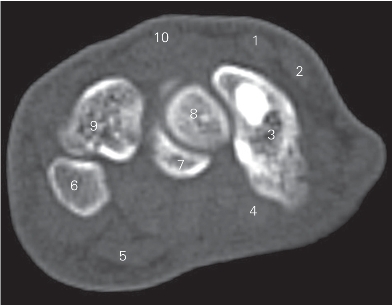

图4-39 经近侧列腕骨的横断层CT图像(骨窗)

1 桡侧腕短伸肌腱 tendon of extensor carpi radialis brevis

2 桡侧腕长伸肌腱 tendon of extensor carpi radialis longus

3 舟骨 scaphoid bone

4 桡侧腕屈肌腱 tendon of flexor carpi radialis

5 尺侧腕屈肌腱 tendon of flexor carpi ulnaris

6 豌豆骨 pisiform bone 7 钩骨 hamate bone

8 头状骨 capitate bone 9 三角骨 triquetral bone

10 指伸肌腱 tendon of extensor digitorum